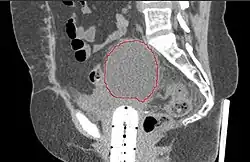

- Postoperative Lymphocele

-